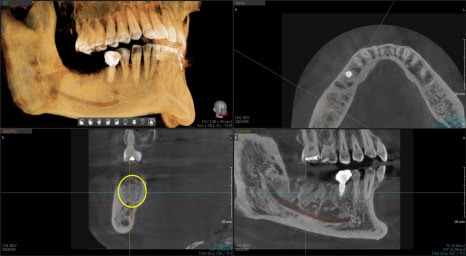

3D CT상에서 치아뿌리 주변 뼈는 염증에 의해 흡수가 되었지만

치아주변을 둘러싸는 4면의 벽은 건전한 편이라 발치 후

치조골이식술을 동반하여 즉시 임플란트 수술이 가능해보였습니다.

노란색으로 표시된 부분이 골 이식재가 단단해져 좋은 환경을 제공해 주었습니다.

아직은 뼈가 단단하진 않기 때문에 좋은위치에 식립한 후